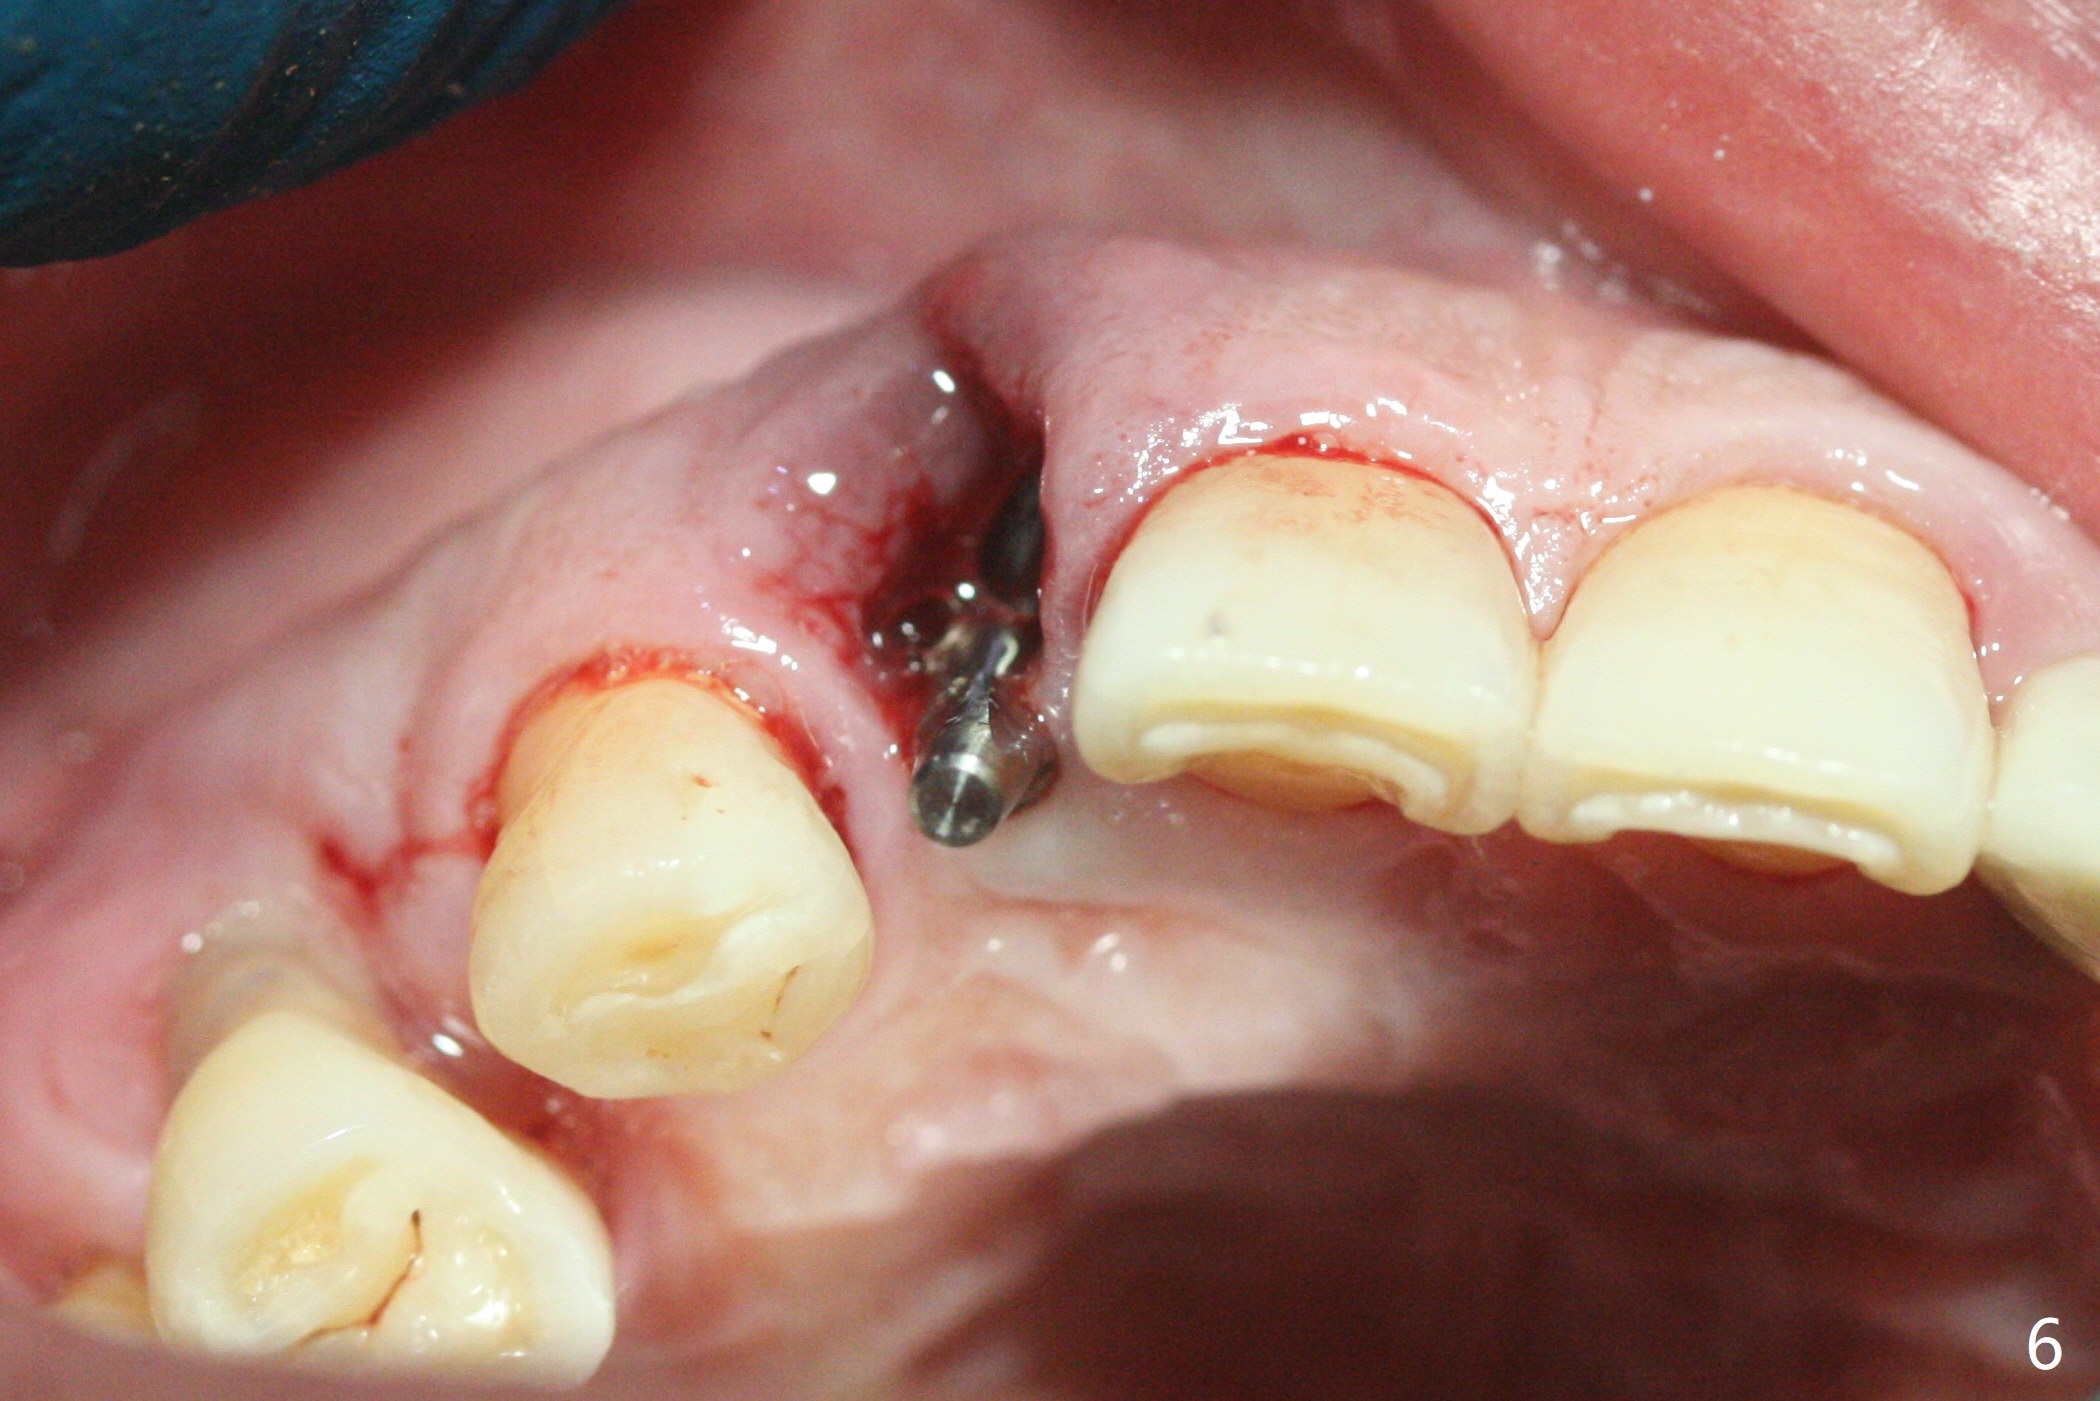

68岁男士右上2严重骨质吸收,颊侧骨板缺失,术前牙龈退缩也十分明显(图一,二),术中对脆弱牙龈缘(图三:*)不应施加任何压力或者牵拉,更不能切开,保持最佳血供。按照术前设计,在牙槽窝腭侧钻洞(图四),植入2.5x15毫米一段式植体(扭力>35Ncm),基台特长(牙龈厚,图五)),基台位于合适修复位置(图六),4-5毫米螺纹颊侧暴露(图七:*)。植骨(图八(CT冠状切面(拔牙后:黑色)):箭头)前,将PRF膜(白线)一头(a)插入牙槽窝颊侧,另外一头(图八,九:b)放置颊侧牙龈颊侧。然后填入粘性骨粉(图九:S;图十四:*),将b头PRF膜往下翻,它末端事先冲一个洞(punch a hole using sterilized rubber dam punch),插入基台(图十(粉红色),十一),这样PRF膜不移位,牢靠地固定骨粉(图十(红圆圈),图十四:*),最后使用树脂敷料覆盖伤口(图十二,十三:A),同样需要基台(箭头,也就是一段式植体)固定,也就是没有即刻植体,就没有骨粉固位。术后两个月伤口缩小,肉芽组织生长(图十五)。撤除树脂敷料后,制作临时牙冠,半个月后唇侧植体有些暴露(图十六),嘱咐强化口腔卫生。